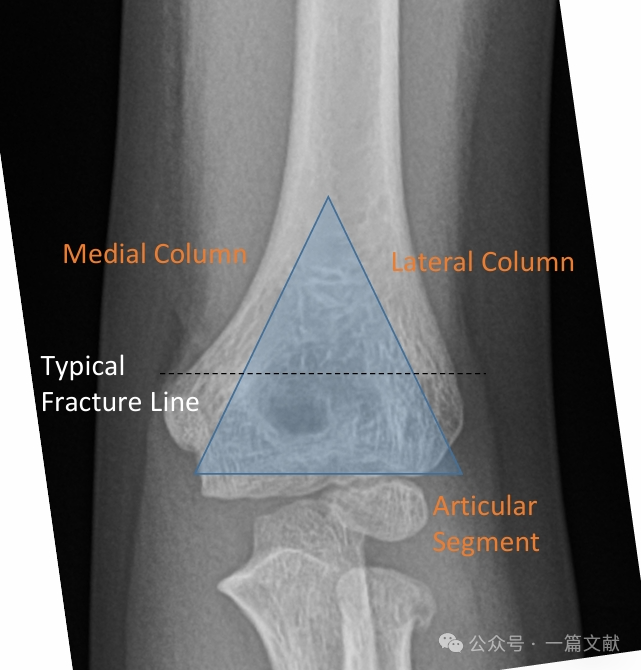

I. Bony Anatomy: The distal humerus is composed of a medial column and a lateral column, which are connected by the articular segment. During fracture, the medial and lateral columns are prone to displacement.

The medial and lateral columns are connected by a thin bone fragment at the olecranon fossa.

* This area represents a structural weak point, making it susceptible to fracture.